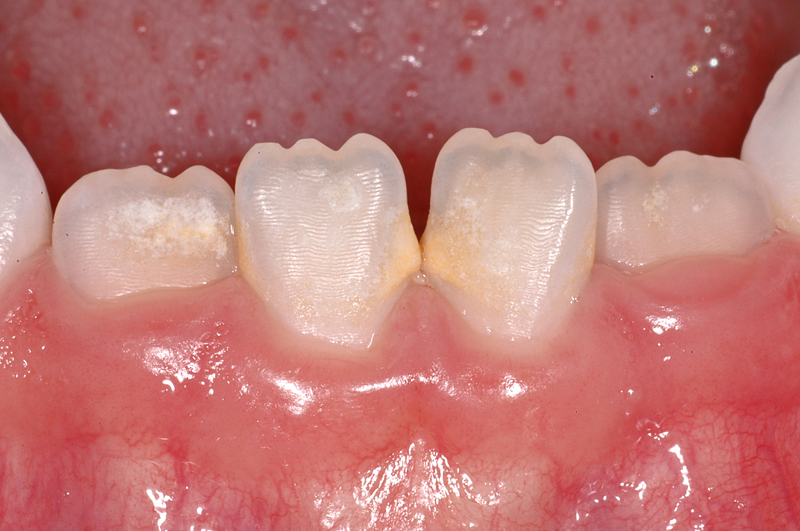

Hier ein Fall mit einer Karies auf der Aussenfläche (Bukkal-Fläche) des linken seitlichen Milchschneide-Zahnes (Zahn 62); das ist die braune, flächige Verfärbung.

Im Zahnzwischenraum «vorne» (mesial) am gegenüberliegenden Zahn 52 ist ebenfalls eine Karies sichtbar.

Ein solches Bild mit Karies an den Glattflächen ist nicht untypisch für die so genannte «Flaschenkaries», verursacht durch ständiges Schoppentrinken oder Nuckeln an Süssgetränken.

Zudem ist bei diesem etwa 7½ Jahre alten Patienten auffällig, dass noch alle Schneidezähne vorhanden sind (verspäteter Zahnwechsel) wie auch, dass die Zähne sehr kurz sind. Das kann z.B. auf «übermässigen Gebrauch» (Knirschen) zusammen mit einer dies begünstigenden Zahnstellung (Kopfbiss) zurückzuzuführen sein, was zur so genannten Abrasion der Zähne führt.

- Karies an 62